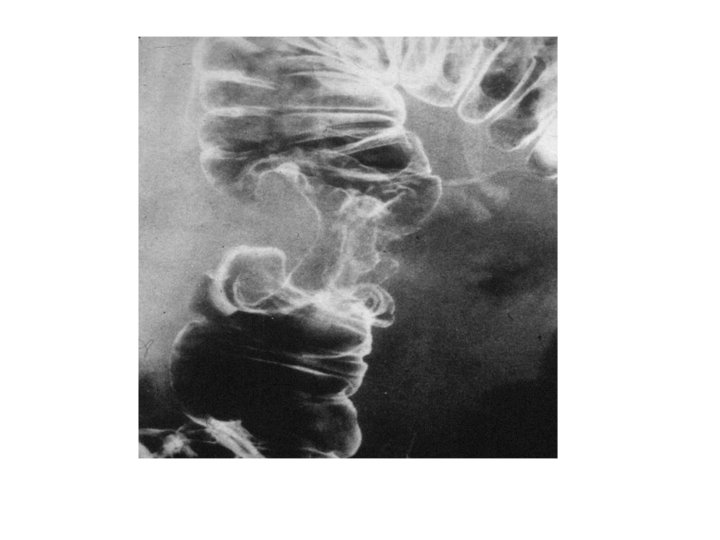

Barium Studies • Barium swallow: used to outline the pharynx and oesophagus. • Barium meal: used to outline the stomach and the first part of the small intestine • Barium follow through: used to outline the small intestine • Barium enema: used to outline the colon

Achalasia • Absent or reduced ganglions within the myenteric plexus • Mostly idiopathic • Can be caused by vitamin B 1 deficiency, Chagas disease and can be congenital • Dysphagia, weight loss, regurgitation • Heller’s procedure